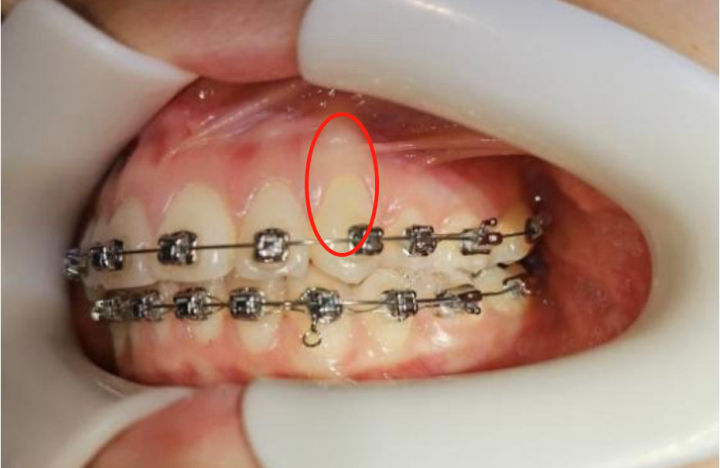

《正畸案例41:正畸中的骨开裂与骨开窗》

《正畸案例41:正畸中的骨开裂与骨开窗》